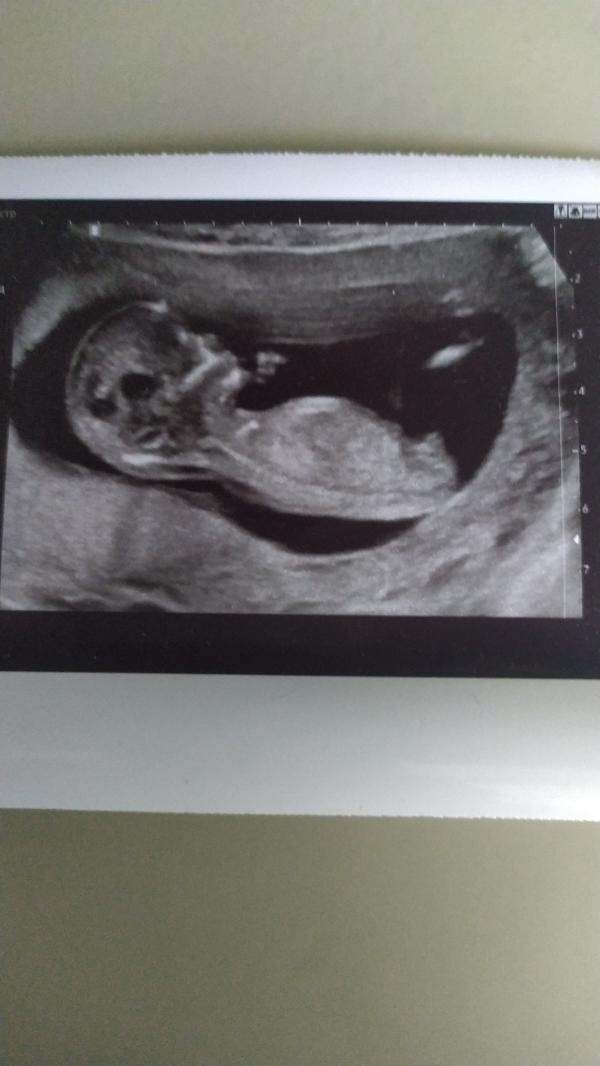

Девочки,как думаете, мальчик или девочка? Узи 12,5 недель. Узи делала в консультации,поэтому пол даже не стали смотреть. Сама сравнила с фото в интернете, кажется на мальчика похож)

Внизу у малыша есть "штучка" так вот если она вверх торчит,значит мальчик,а если горизонтально расположена,значит девочка.

По такому расположению не понятно, вид с низу ягодиц и промежности обычно может сказать пол